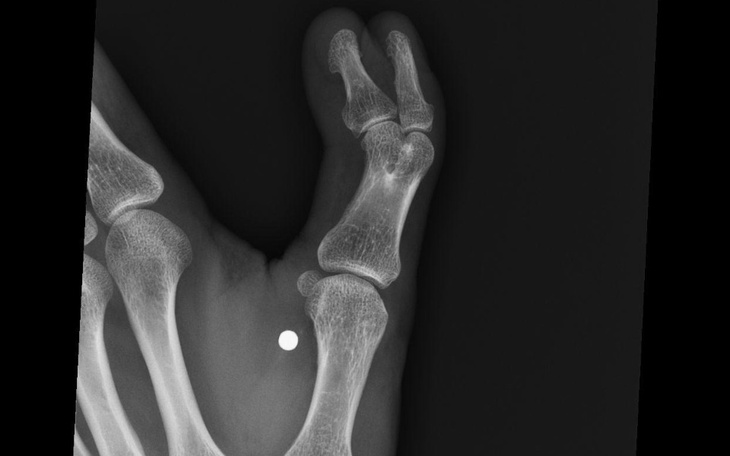

Witam wszystkich od dziecka zmagam się z bardzo wstydliwą chorobą a mianowicie posiadam dodatkowo jeden palec u lewej dłoni . Gdy byłem dzieckiem zabieg był nie możliwy ponieważ palec jeszcze się rozwijal i musiał się po prostu dokładnie rozwinąć,wczesna operacja mogłaby spowodować problem z prawidłowym rozwijaniem prawidłowego palca.. Gdy byłem młodzieńcem operacja miała dojść do skutku jednak wstyd nie pozwolił mi pokazać tego palca nawet lekarzowi. Tak mijały lata , aż do teraz postanowiłem pokonać wstyd i zrobić z tym porządek jednak próbując zrobić operację na fundusz zdrowia usłyszałem diagnozę iż będę musiał czekać na zabieg nawet kilka lat. Chciałabym zacząć żyć normalnie i przestać ukrywać się z moim dodatkowym palcem,dlatego proszę wszystkich o pomoc, niestety brakuje mi środków na operację która może wynieść nawet 15 tysięcy zloty(operacja około 8-9 tysięcy plus wizyty u lekarzy i późniejsza rehabilitacja .Celem zbiórki jest 12 tys gdyż pozostala część kwoty postaram się pokryć sam. Bardzo proszę o pomoc i jednocześnie dziękuję.🤗